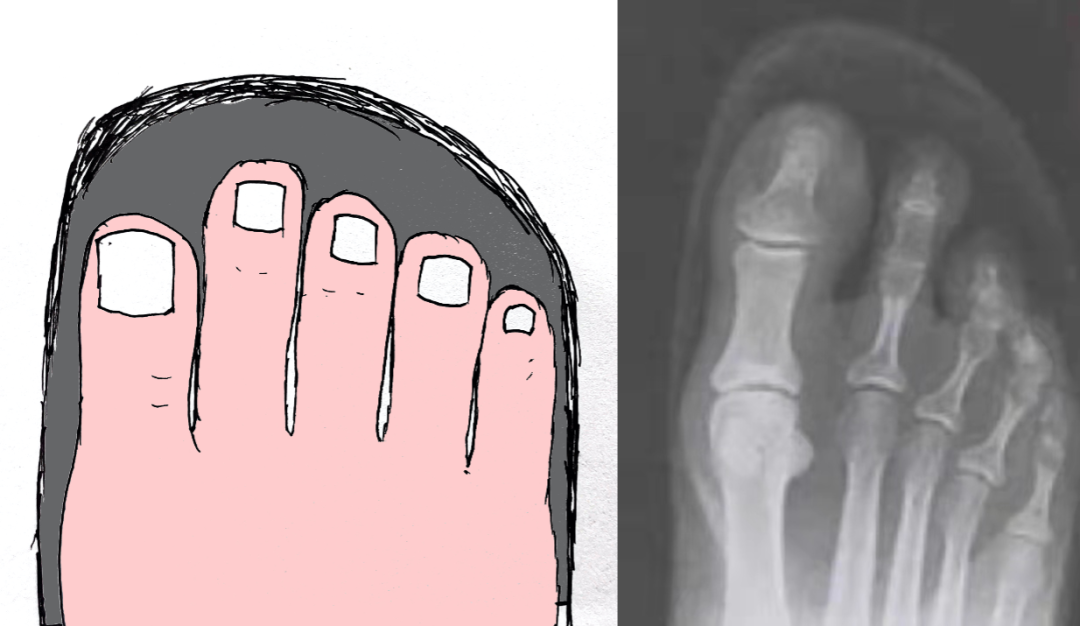

趾甲解剖

临床表现 (分 3 期)